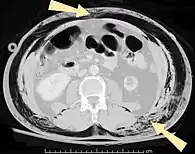

Scanner abdominal (rayons X) d'un patient présentant un emphysème sous-cutané (flèché) | |

Les cas importants d'emphysème sous-cutané sont faciles à diagnostiquer en raison des signes caractéristiques de l'affection. Dans certains cas, les signes sont subtils, ce qui rend le diagnostic plus difficile. L'imagerie médicale est utilisée pour diagnostiquer la maladie ou confirmer un diagnostic établi à l'aide de signes cliniques. Sur une radiographie du thorax, l'emphysème sous-cutané peut être vu comme des stries radiotransparentes dans le modèle attendu du groupe de muscles principaux du pectoral. L'air présent dans les tissus sous-cutanés peut interférer avec la radiographie du thorax, ce qui peut masquer des affections graves comme le pneumothorax. Elle peut également réduire l'efficacité de l'échographie thoracique. D'autre part, comme l'emphysème sous-cutané peut être visible sur les radiographies du thorax avant un pneumothorax, sa présence peut être utilisée pour déduire celle de cette dernière lésion. L'emphysème sous-cutané peut également être observé sur les scanners, les poches d'air apparaissant comme des zones sombres. Le scanner est si sensible qu'il permet généralement de trouver l'endroit exact d'où l'air pénètre dans les tissus mous. En 1994, M. T. Macklin et C. C. Macklin ont publié d'autres aperçus sur la physiopathologie du syndrome de Macklin spontané survenant à la suite d'une grave crise d'asthme. La présence d'un emphysème sous-cutané chez une personne qui semble très malade et fébrile après une crise de vomissements suivie d'une douleur thoracique gauche est très évocatrice du diagnostic du syndrome de Boerhaave, qui est une urgence vitale causée par une rupture de l'œsophage distal. L'emphysème sous-cutané peut être une complication de l'insufflation de CO2 avec la chirurgie laparoscopique. Une augmentation soudaine du CO2 en fin de marée après la hausse initiale qui se produit avec l'insufflation (les 15-30 premières minutes) devrait faire suspecter un emphysème sous-cutané. Il est à noter que l'oxymétrie de pouls et la pression des voies aériennes ne varient pas dans l'emphysème sous-cutané, contrairement à l'intubation endobronchique, au capnothorax, au pneumothorax ou à l'embolie au CO2.